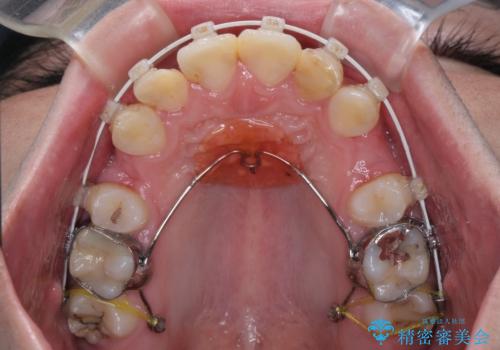

- 審美装置

口元はやや突出感があったため、上下左右の第一小臼歯4本を抜歯してワイヤー矯正にて抜歯矯正を行うこととしました。

また、左右ともに最後臼歯が交叉咬合になっており、外側に飛び出している上顎の最後臼歯を補助装置を利用して、積極的に内側に引き込むようにしました。